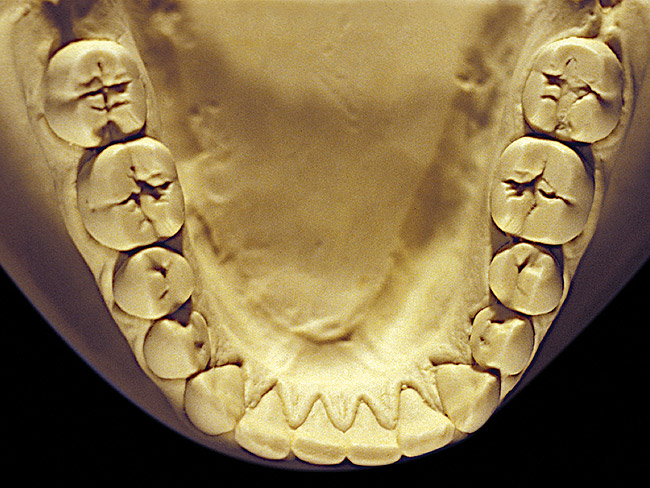

The patient shown in Figure 3 and Figure 4 exhibited severe NCLTS from bruxism. Examination of the casts indicated that the NCLTS was progressively greater toward the anterior teeth. Cupping and cratering was not present because there was no secondary cause. Figure 5 and Figure 6 detail another bruxism patient, but to a lesser degree and one with cupping/cratering caused by toothpaste. The cups or craters were not caused from bruxism because the teeth could not touch the bottom of the invaginations. In both featured patients, upon hand-articulating the casts, the NCLTS facets matched up and the diagnosis of bruxism was confirmed.

Figure 2  Advanced NCLTS from bruxism, mandibular arch.

Figure 2